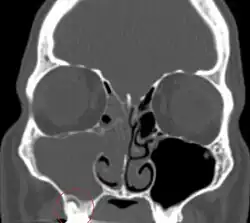

Diagnosis

The diagnosis of odontogenic sinusitis is often challenging and requires a multidisciplinary approach involving otolaryngologists and dental specialists. Clinical examination and patient history play a crucial role.[11] Radiological investigation, including dental panoramic radiographs, computed tomography scans, and cone-beam computed tomography can help visualize the relationship between the maxillary sinuses and the dental structures, identify dental pathologies, and assess the extent of sinus involvement.[1]